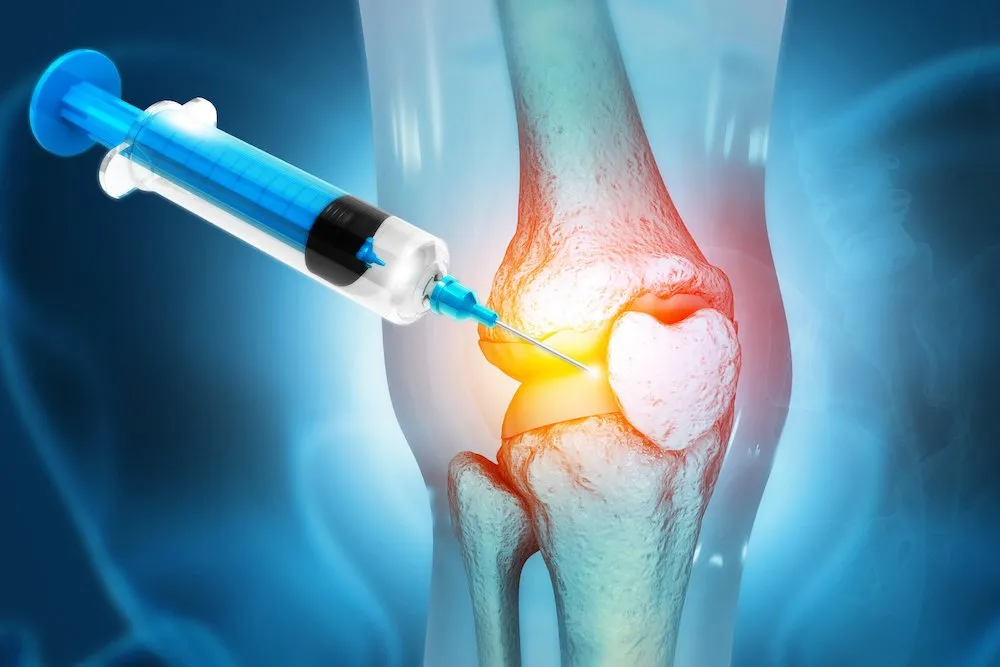

تزریقات مفصلی

تزریقات مفصلی یکی از روشهای پیشرفته و موثر برای درمان آسیبهای مفصلی و کاهش درد مزمن است. این روشها با هدف بازگرداندن حرکت طبیعی مفصل، کاهش التهاب و بهبود کیفیت زندگی بیماران استفاده میشوند. تزریقات مفصلی به عنوان جایگزینی غیرجراحی، روند درمان را تسریع کرده و از نیاز به جراحی در بسیاری از بیماران جلوگیری میکند.

در کلینیک فیزیوتراپی خانه سلامت، تزریقات مفصلی با استفاده از روشهای نوین مانند PRP، اوزوندرمانی، تزریق ژل داخل مفصلی و دیسکوژل انجام میشود. این خدمات با رعایت بالاترین استانداردهای پزشکی ارائه میشوند تا بهترین نتیجه درمانی حاصل شود.

تزریق ژلهای داخل مفصلی

تزریق ژل داخل مفصل روشی موثر برای بهبود حرکت و کاهش درد ناشی از آسیب یا آرتروز مفصلی است. این ژلها با روانسازی مفصل، اصطکاک را کاهش داده و حرکت طبیعی مفصل را بازمیگردانند. این روش به بیماران کمک میکند تا زندگی فعالتر و بدون دردتری داشته باشند.

تزریق ژل داخل مفصل معمولاً برای بیمارانی که نیاز به کاهش درد طولانی مدت دارند، کاربرد دارد. در کلینیک خانه سلامت، این تزریقات با تکنیکهای دقیق و استفاده از مواد استاندارد انجام میشود تا بهترین نتیجه درمانی حاصل گردد.